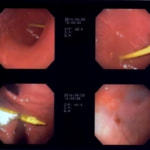

11歳 ミニチュア・ダックス 去勢オス

主訴:焼き鳥の竹串を食べたとの事で来院しました。元気・食欲は問題なく、嘔吐などの症状もありませんでした。便にも竹串が1/3程でているとの事でしたが、全ての竹串が出ていないため、内視鏡検査を実施致しました。

内視鏡検査所見:胃内に竹串の先端部分が残っていたため、異物鉗子にて摘出しました。胃内は、全体的に炎症を伴い、出血している部位も確認されました。摘出後は、胃粘膜保護薬・プロトンプインヒビター(胃薬)の内服2剤ならびに食事療法により経過は良好です。

摘出した竹串

内視鏡下写真

◎竹串誤飲は、異物の1位と言われるほど多く認められています。竹串は、先端が尖っているため消化管穿孔などを起こし、命に関わることもあります。万が一、ご自宅や散歩中に串などを食べてしまった場合は、病院まですぐご連絡下さい。また竹串は、食道を傷つけ・穴をあける恐れなどもあるため無理に吐かせる事は絶対にしないで下さい。本症例は、内視鏡下にて摘出が可能でしたが、状況によっては開腹が必要となる場合もあります。